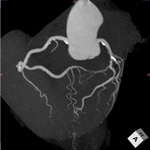

■ 冠動脈解析ソフト

最新の冠動脈解析ソフトではフルオート処理の精度がさらに向上しました。データの読み込みから冠動脈の抽出、CPR・ストレートビュー表示、アンギオ様のMIP「Angio Graphic View(AGV)」表示までのフルオート高速処理がさらに進化し、より精度の高いAGV画像を得ることができます。新機能「エクステンダー」ではMIP、VR、2Dのいずれかの画像上でマウスボタンを押し続けるだけで細血管を追加、修正することができます。新しい修正ツールでは細部の修正がより簡便になりました。

冠動脈解析ソフト